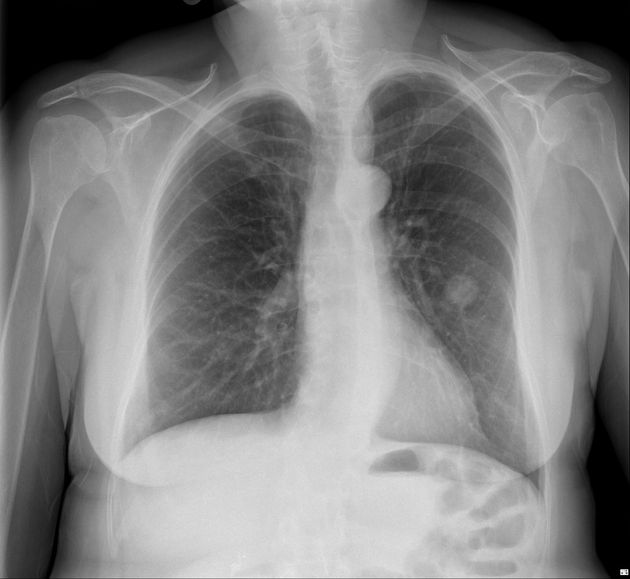

Любого доктора можно быстро подготовить как рентгенлаборанта и дать необходимые знания для оценки рентгенограмм.

Изучение проблемы низкого качества рентгенограмм на Вашем оборудовании.